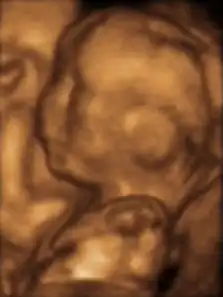

Le diagnostic de RCIU est le plus souvent évoqué devant la découverte d'une hauteur utérine insuffisante pour le terme. Cette hypothèse de RCIU doit être distinguée du petit poids pour l'âge gestationnel[41]. Parfois, c'est au cours du bilan d'une maladie connue pour ses risques de RCIU, à l'occasion d'une échographie obstétricale systématique, au cours du bilan d'une infection materno-fœtale, etc. Le diagnostic est affirmé par la mesure des biométries fœtales : périmètre abdominal, diamètre bipariétal, périmètre crânien, longueur du fémur. La biométrie fœtale doit être comparée à la taille et au morphotype parental. L'examen recherche aussi des causes locales de RCIU (malformation utérine, grossesse gémellaire), apprécie les possibilités de croissance fœtale par l'étude doppler d'une artère ombilicale et recherche par l'étude des artères utérines les causes vasculaires en rapport avec une hypertension artérielle gravidique. L'étude soigneuse de la morphologie fœtale permet parfois de rattacher le RCIU à un syndrome malformatif. Si l'examen ne met pas en évidence d'anomalie fœtale, il faut évaluer le bien-être fœtal à un rythme qui dépend de la sévérité et du type de RCIU.